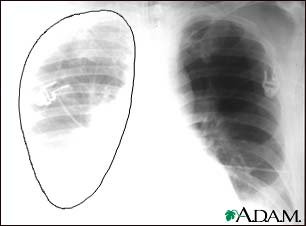

Aortic rupture (a tear in the aorta, which is the major artery coming from the heart) can be seen on a chest x-ray. In this case, it was caused by a traumatic perforation of the thoracic aorta. This is how the x-ray appears when the chest is full of blood (right-sided hemothorax) seen here as cloudiness on the left side of the picture.